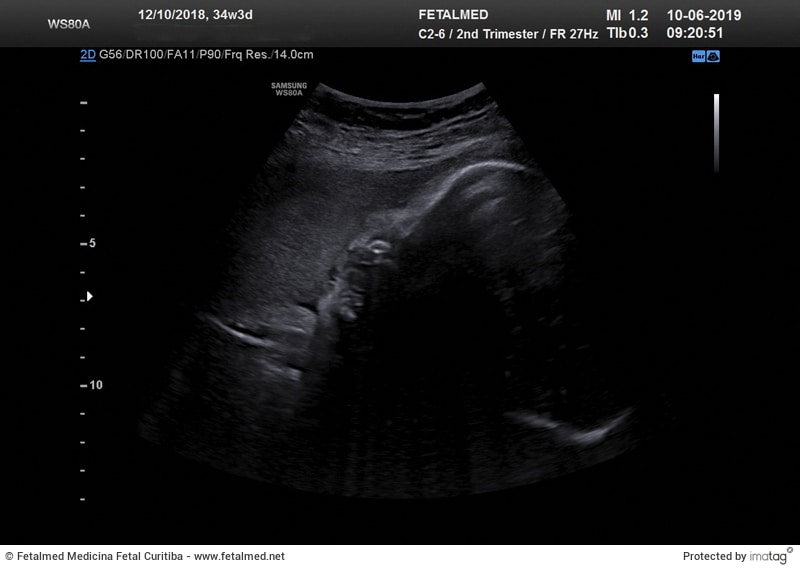

Selecionamos abaixo algumas imagens, feitas no mesmo aparelho, por vezes durante o mesmo exame. Entretanto o resultado é completamente diferente, quando não havia condição ideal para a formação de uma imagem.

Aqui novamente a face do bebê encontrava-se completamente encostada na parede do útero, sem líquido na sua frente. Isso fez com que a imagem do perfil do bebê ficasse bastante comprometida e de difícil compreensão.